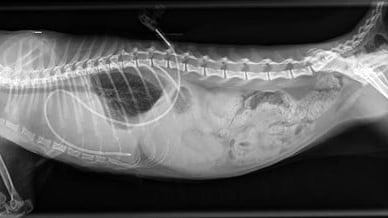

Kat 2: een Britse korthaar kater van 8 maanden kreeg koorts, wilde niet meer spelen en werd snel slomer. Hij ademde wat snel en op röntgenfoto’s van de borstkas werd vrij vocht gezien. Punctie leverde heldere, waterige vloeistof op, waardoor de dierenarts aan een hartprobleem dacht. Maar echografie liet geen afwijkingen van het hart zien. Wel vergrote lymfeknopen, verdikte pleurabladen en het vocht leek niet meer helder (1 dag later). Punctie leverde nu wat pussige vloeistof op. Celonderzoek liet een aspecifieke ontsteking zien en bij bacteriologisch onderzoek werd Actinomyces gevonden (waarschijnlijk niet de primaire oorzaak). Er werd een drain geplaatst en enkele dagen afgezogen en therapie met prednison werd gestart. Bloedonderzoek liet gestegen totaal eiwit en gamma globulines zien en gedaald albumine.

Röntgenfoto met vrij vocht en thoraxdrain

Na verwijderen vocht uit thorax

Een week na start therapie